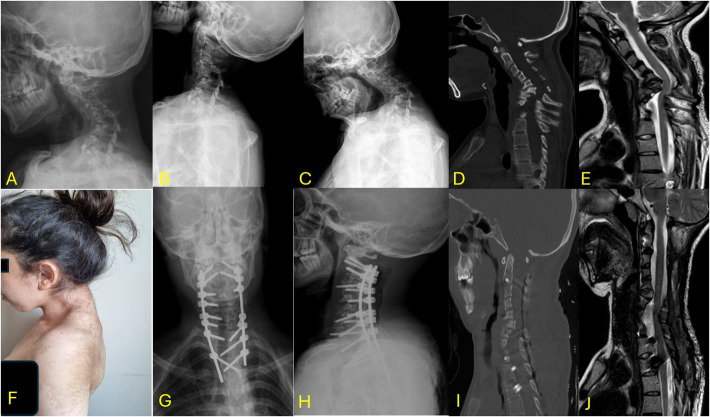

Abstract Image